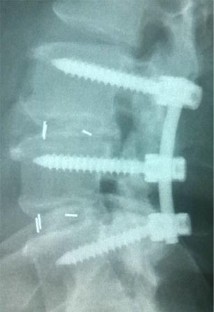

Fig. 4